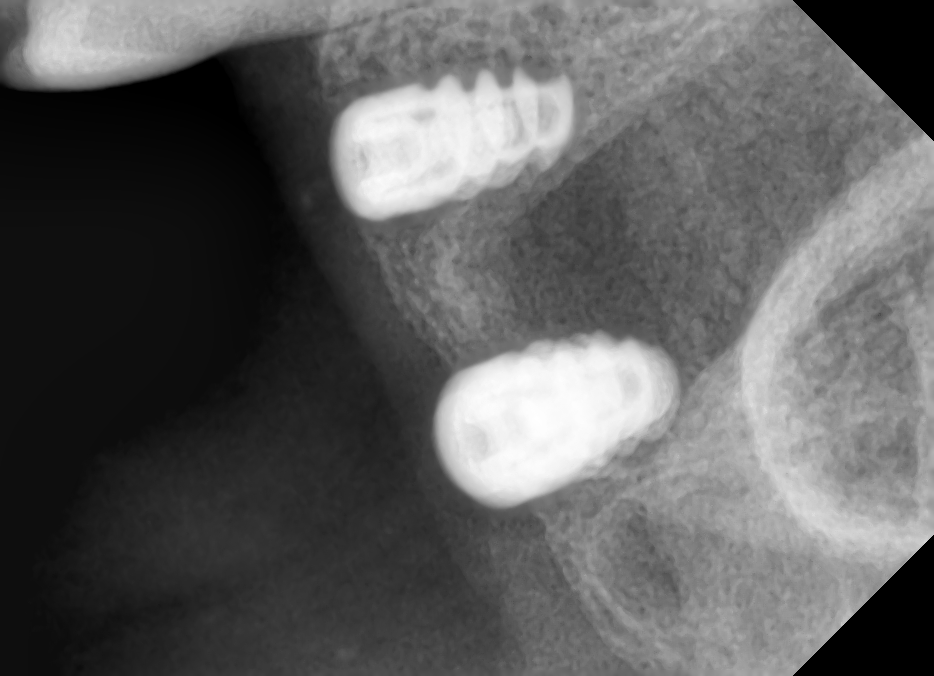

implantes en 4 cuadrante

Paciente de Idental que ha llegado a nuestra consulta. Colocados hace 2 o 3 años en Madrid